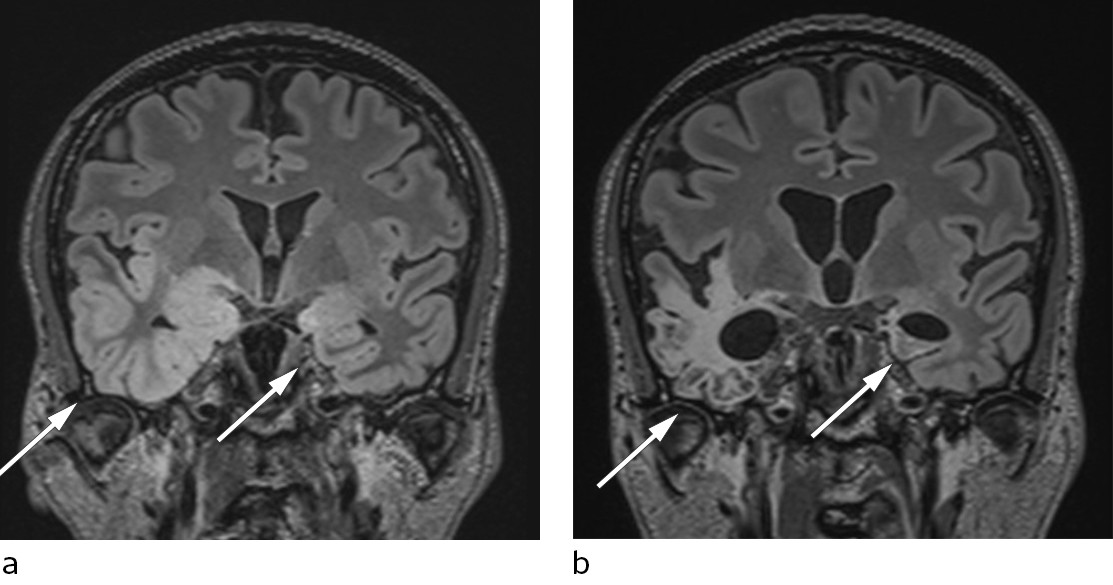

The EEG showed pathological slowing of background activity and bursts of delta activity in temporal regions, consistent with encephalitis (6, 7). A head MRI performed six days after admission showed widespread changes over the temporal lobes, including the hippocampus, typical of herpes encephalitis (8) (Figure 2, Figure 3a).

A week after initiation of immunoglobulin therapy, high NMDA receptor antibody titres were confirmed in the patient's CSF. Another brain MRI four weeks after the first showed increasing hyperintensities in both temporal lobes. This finding is not specific to either herpes encephalitis or autoimmune encephalitis (11).

The patient's condition eventually stabilised, but although rehabilitation was attempted several times, he never recovered sufficient function to be able to return home. He now lives in supported housing where he requires intensive follow-up. An MRI scan 4.5 months after symptom onset revealed extensive damage to both temporal lobes (Figure 3b).

In our patient, it was probably the viral encephalitis that was responsible for most of the lasting damage (Figures 3a and b).